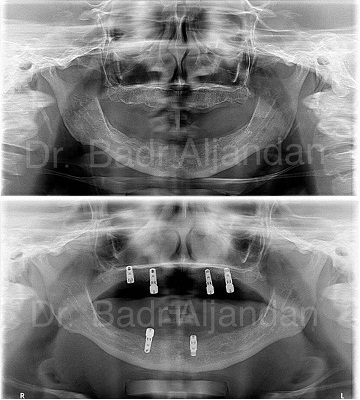

For most patients, the placement of dental implants involves two surgical procedures. First, implants are placed within your jawbone. For the first three to six months following surgery, the implants are beneath the surface of the gums gradually bonding with the jawbone. You should be able to wear temporary dentures and eat a soft diet during this time. At the same time, your dentist is forming new replacement teeth.

After the implant has bonded to the jawbone, the second phase begins. Dr. Al-jandan will uncover the implants and attach small posts that protrude through the gums and will act as anchors for the artificial teeth. When the artificial teeth are placed, these posts will not be seen. The entire procedure usually takes six to eight months. Most patients experience minimal disruption in their daily life.

A single prosthesis (crown) is used to replace one missing tooth – each prosthetic tooth attaches to its own implant. A partial prosthesis (fixed bridge) can replace two or more teeth and may require only two or three implants. A complete dental prosthesis (fixed bridge) replaces all the teeth in your upper or lower jaw. The number of implants varies depending upon which type of complete prosthesis (removable or fixed) is recommended. A removable prosthesis (over denture) attaches to a bar or ball in socket attachments, whereas a fixed prosthesis is permanent and removable only by the dentist.